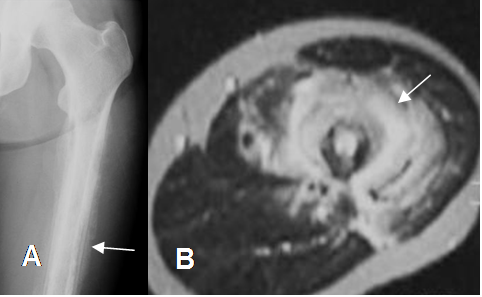

En el diagnostico diferencial de las lesiones óseas, se debe incluir siempre la osteomielitis en sus diferentes etapas. (4, 12). (Fig 32).

Fig 32. Osteomielitis.

A: Rx AP y B: RM axial en T2. Reacción perióstica en capas de cebolla en la diáfisis femoral, con cambios inflamatorios en los tejidos blandos, que sugiere proceso neoplásico, pero producidos por una osteomielitis.